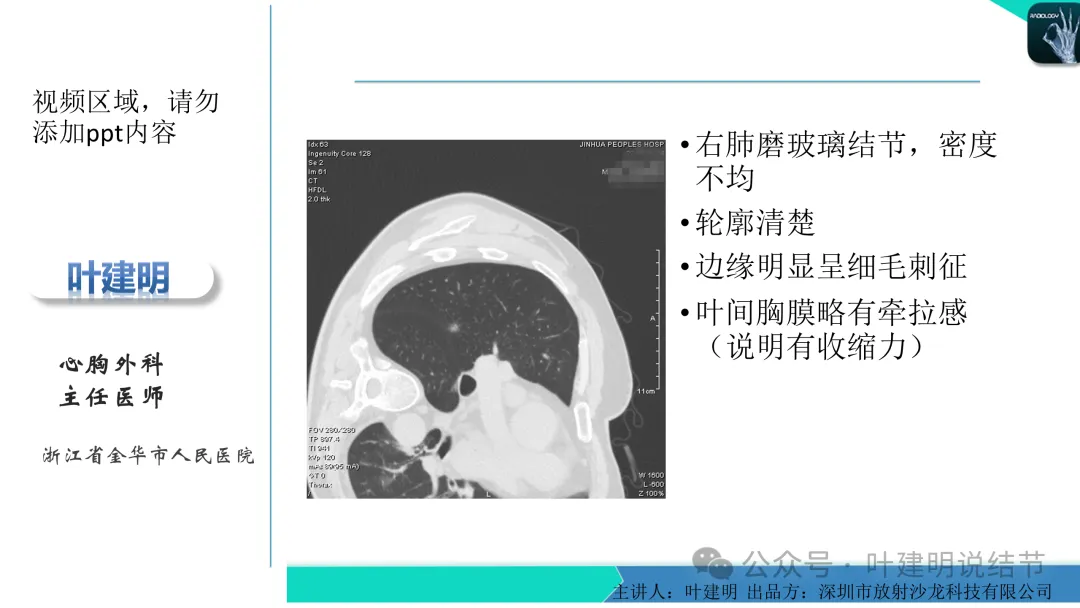

早在2020年时,我受邀在《放射沙龙》做过一个系列的精品课,当时专门总结分析过各类良恶性肺结节与肿块的影像特征,这是当时关于微浸润性腺癌影像特征的分析,今天看来仍基本不太需要改变,大家有兴趣的可以参考: